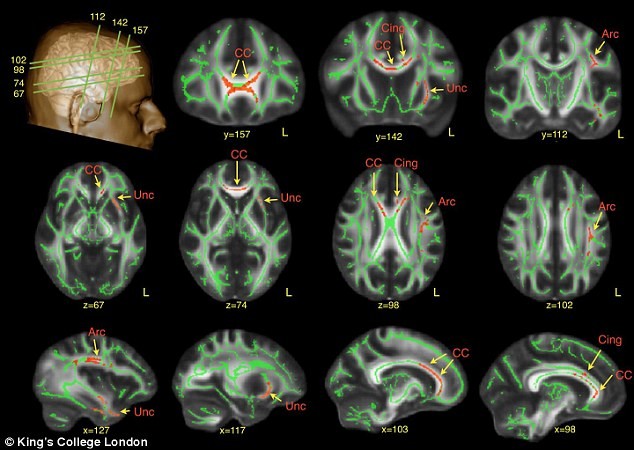

محققان از اسکنهای MRI برای مطالعه مغز بزرگسالان مبتلا به اتیسم استفاده نموده و دریافتند که تفاوتهای ویژه ای در نقاط کلیدی ماده سفید مغز این اشخاص، که درگیر با گفتار و تشخیص چهره می باشند، وجود دارد. نواحی قرمز رنگ در مناطق درخشان اسکنهای فوق اختلافات یافته شده را نشان می دهد.

نوروسافاری| تصاویر اسکن مغزی مبتلایان به اتیسم تغییرات ظریفی را در مناطقی از مغز که دخیل در گفتار و شناسایی چهره می باشند، آشکار ساخت.

·         دسته-مسیرهای عصبی مختص گفتار و پردازش تشخیص چهره آسیب دیده بودند.

محققان به ویژه متوجه شدند که در افراد مبتلا، ارتباط  بین سلولهای عصبی در ناحیه ای از سمت چپ مغز، که دسته آرکوئیت نامیده شده و مسئول گفتار می باشند، نسبت به افراد سالم دچار تغییر شده اند. این تفاوتها خصوصاَ در مبتلایانی که در طی دوره بیماری خود  “ﭘﮋواک ﮔﻮﯾﯽ ﺑﺎ ﺗﺎﺧﯿﺮ” را  تجربه نموده بودند، بطور  شدیدتری نمود داشت (موردی که مبتلایان غالباً کلمات یا جملات را طوطی وار تکرار می کنند).

ماده سفید در کمک به برقراری اتصال بخشهای مختلف مغز با یکدیگر نقشی حیاتی ایفا کرده و به این بخشها اجازه می دهد با یکدیگر ارتباط برقرار کنند. این اسکن ها همچنین آشکار ساختند که افراد با طیف اختلال اتیسم، رشد کمتری را در ماده سفید مغز، در بخشهایی از مغز که دسته چنگکی سمت چپ (the left uncinated bundle) نامیده می شود، داشتند. این بخش نقش چشمگیری را در تشخیص چهره و پردازش حسی ایفا می کند.